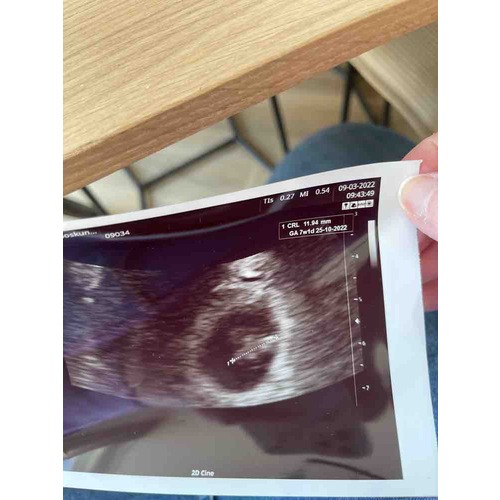

Ik heb ook een gekantelde baarmoeder daar kwamen ze achter bij het plaatsten van de spiraal en is bij de eerste echo nog eens bevestigd. In het begin konden ze het vruchtje niet zo goed meten er zat 2 weken verschil tussen de metingen.